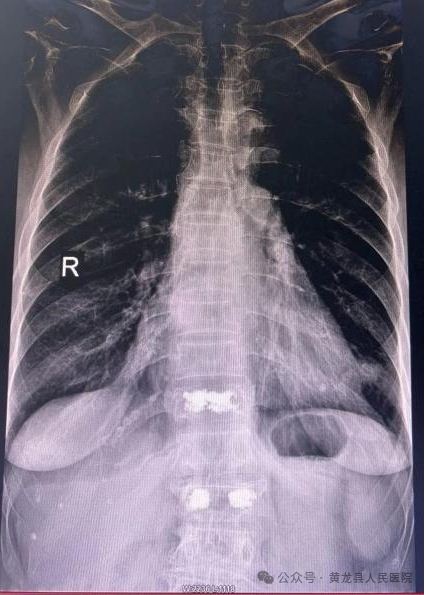

患者女,78岁,2023年3月不慎摔倒致胸腰背部疼痛,翻身、弯腰、下地活动严重受限。入院后X线检查示:腰1椎体压缩性骨折,结合患者具体情况,给予综合评估,给予微创经皮椎体成形手术,手术效果满意。2023年8月,患者再次不慎摔伤,致胸11椎体骨折,有了第一次微创手术经历,患者入院后果断选择微创经皮椎体成形手术治疗,手术顺利,达到预期效果,术后患者恢复较好,经过外科医护团队精心治疗和优质护理,患者顺利出院。患者及家属对整个就医感受很是满意,特送上锦旗向医务人员表示感谢。

术前MRI 和术后X线影像图片

患者女,88岁,因病理性骨质疏松导致胸腰背部疼痛,翻身、弯腰、下地活动严重受限。入院后行X线检查示:胸椎体压缩性骨折(胸11)。

术前术后X线影像